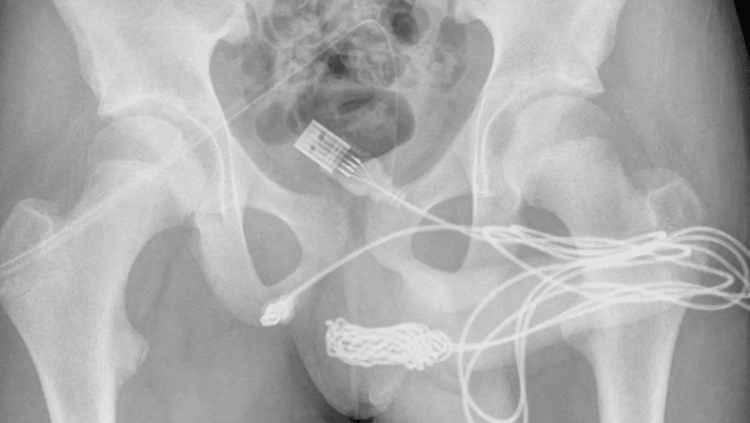

Segundo a revista “Urology Case Reports”, um jovem britânico foi parar em uma mesa de cirurgia após inserir um cabo USB no pênis, porque queria medir o tamanho do órgão.

Essa “experiência” não ocorreu como planejado e o jovem acabou prendendo o cabo no membro. Ele ainda tentou tirar o USB, mas acabou piorando a situação, prendendo o cabo em sua uretra.

O jovem passou a urinar sangue, o que fez com que seus pais o levassem ao centro de urgência para o hospital. O garoto, com vergonha, disse aos médicos que tinha inserido o cabo na uretra para fazer a medição por curiosidade.

Os médicos realizaram uma uretrostomia penoescrotal, onde é feito um corte entre a genitália e o ânus do paciente. O cabo foi retirado com sucesso e o jovem recebeu alta no dia seguinte, sem sequelas.